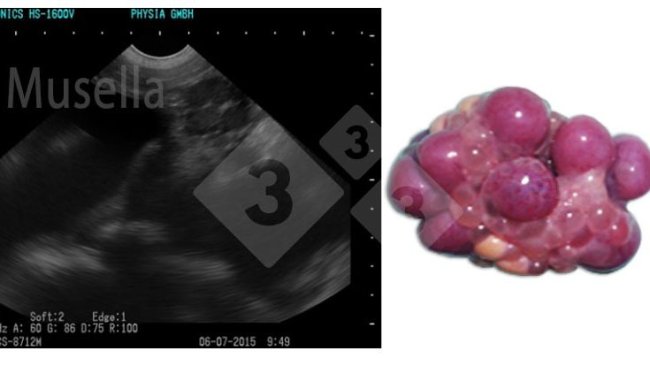

Relativamente às novas técnicas com ecógrafos de alta definição, que são capazes de identificar o estado do ciclo da porca (pode ser realizada a inseminação pouco antes ou na ovulação), cientificamente são métodos de grande valor, mas com uma grande necessidade de qualificação da pessoa que o realiza e um alto nível de disponibilidade de pessoal, uma vez que o acompanhamento do crescimento folicular e, portanto, do momento do ciclo estral, requer várias observações diárias, o que dificulta sua implementação na exploração.